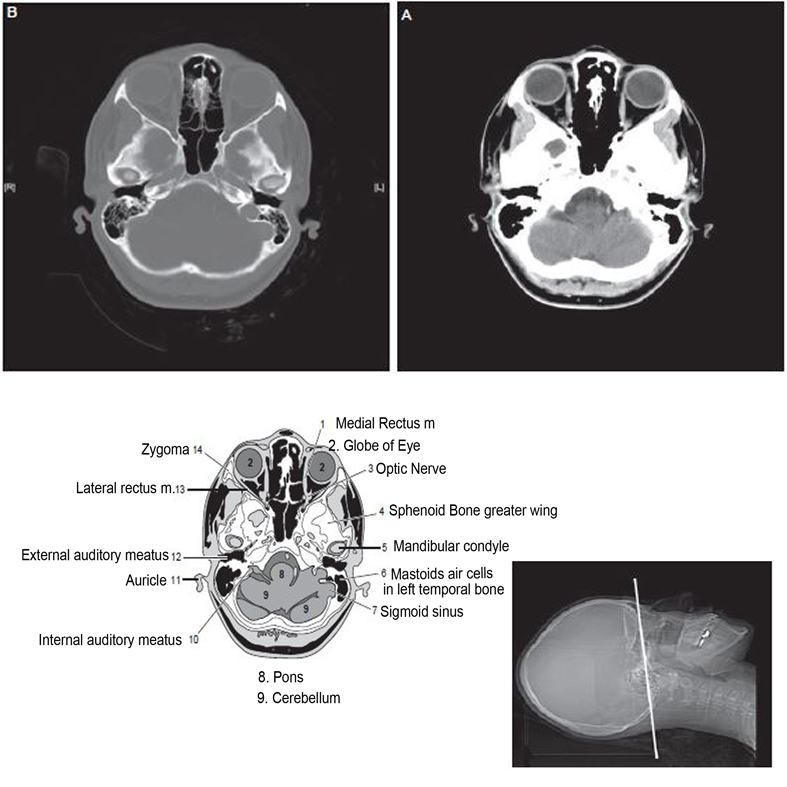

Figure 1 from MR and CT anatomy and the pathology of skull base Ct Anatomy Face The acquisition parameters are as follows: This head and neck anatomy atlas is an educational tool for studying the normal anatomy of the face based on a contrast enhanced multidetector computed tomography imaging. This study is a normal ct of the face without intravenous contrast. At the time the case. Annotated teaching ct head in standard and bone windows. Head. Ct Anatomy Face.

Axial CT bone window of skull base from inferior to superior aspect Ct Anatomy Face Normal ct head with annotated and original images. In noncontrast head ct, axial images are the routine series. This study is a normal ct of the face without intravenous contrast. In facial ct, both axial and coronal views are routinely provided for interpretation; Head first supine scan range: Anatomy labelled radiographs and ct/mri series teaching anatomy with a level of. Ct Anatomy Face.

Axial CT bone window of skull base from inferior to superior aspect Ct Anatomy Face Annotated teaching ct head in standard and bone windows. In noncontrast head ct, axial images are the routine series. Head first supine scan range: The acquisition parameters are as follows: This head and neck anatomy atlas is an educational tool for studying the normal anatomy of the face based on a contrast enhanced multidetector computed tomography imaging. At the time. Ct Anatomy Face.